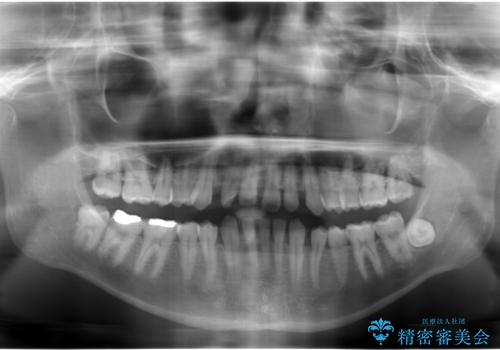

すきっ歯・出っ歯 コンプレックスの前歯を治したい 目立たない方法で セラミック治療は不可能な症例

- 前歯の並びを治したいと来院。

人前に立つ予定があるとのことで、初めはセラミックで歯を削ってかぶせる短期間で終える治療を希望されていました。

歯の位置が悪く、隙間も大きいためセラミックで被せても到底思ったような仕上がりにならないこと、下の歯が咬み込んでいるためセラミックはおろか前歯が短期間で折れてしまうリスクが非常に高いことを説明しました。

まだ20代と若く、これから歯をずっと使っていくことを踏まえて、前歯の角度や位置をしっかり変える矯正治療をおすすめしました。

上はインビザラインで目立たないように前歯を下げ、下は難しいため、ワイヤー矯正で咬み込んでいる下の歯を沈める処置を初め行いました。最終的には上下ともインビザライン矯正で仕上げました。

下の前歯が生まれつき1本少なかったため、その部分には最終的にインプラントを入れ、下の歯が下がりすぎないようにかつ上の前歯にしっかり咬むように仕上げました。